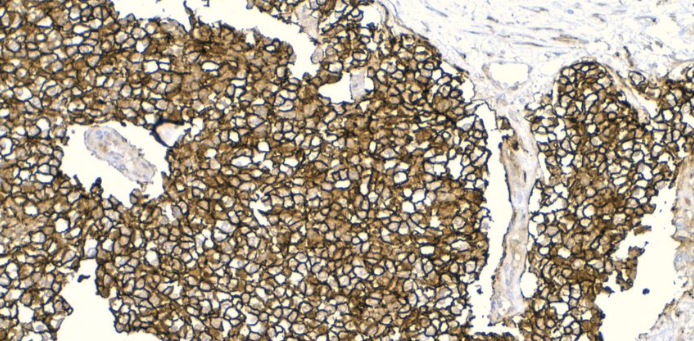

Ewing Sarcoma CD99 positive

[EWING’S SARCOMA/PNET, BONE] – The neoplastic cells are small to intermediate in size with scant cytoplasm, indistinct cell membranes, round to slightly angulated nuclei containing indistinct to small nucleoli. The cells may be so undifferentiated that a morphologic distinction from any of the other small blue round cell tumors may be impossible on morphology alone. However, pseudo- rosette or true rosette formation may be present suggesting a neuroectodermal differentiation. In some tumor, however, mild pleomorphism is present with divergent immunohistochemical differentiation.

[EWING’S SARCOMA/PNET, BONE] – The tumor cells are rather undifferentiated morphologically and are arranged in large sheets and clusters separated by thick fibrous bands. Necrosis may be focal or extensive (arrowhead) and may render diagnosis difficult in small biopsy specimens with few viable cells. FISH study for typical t(11;22) may prove diagnostic in smaller samples.